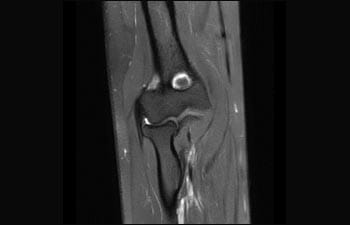

Conozca cómo Ingenia Prodiva puede satisfacer sus necesidades clínicas.

Conozca la opinión de los primeros usuarios de Ingenia Prodiva 1.5T acerca de sus experiencias con el sistema y cómo influye este en su centro de diagnóstico por imagen.

1De acuerdo con un estudio interno en el que se compara el flujo de trabajo con el equipo de RM Achieva. 2 ComforTone estará disponible con Prodiva 1.5T en el cuarto trimestre de 2017 3 De acuerdo con un estudio interno donde se compara el flujo de trabajo en una combinación de aplicaciones cerebrales, musculoesqueléticas, de columna y de cuerpo con el equipo de RM Achieva 4 La operación normal se define como una adquisición típica realizada con suministro continuo de electricidad, así como de refrigeración del imán, sin incluir las actividades de servicio 5 En función del contrato y de la disponibilidad local 6 Con "otros equipos de RM" nos referimos a equipos de RM de 1,5 T de 60 cm para exámenes de cuerpo entero